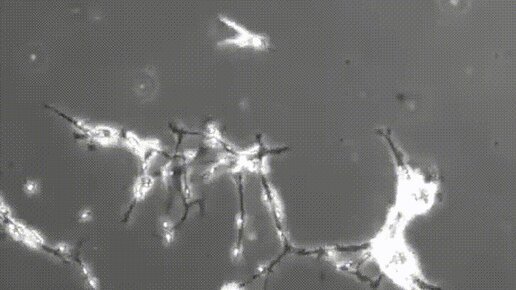

Возникновение новой нейронной связи